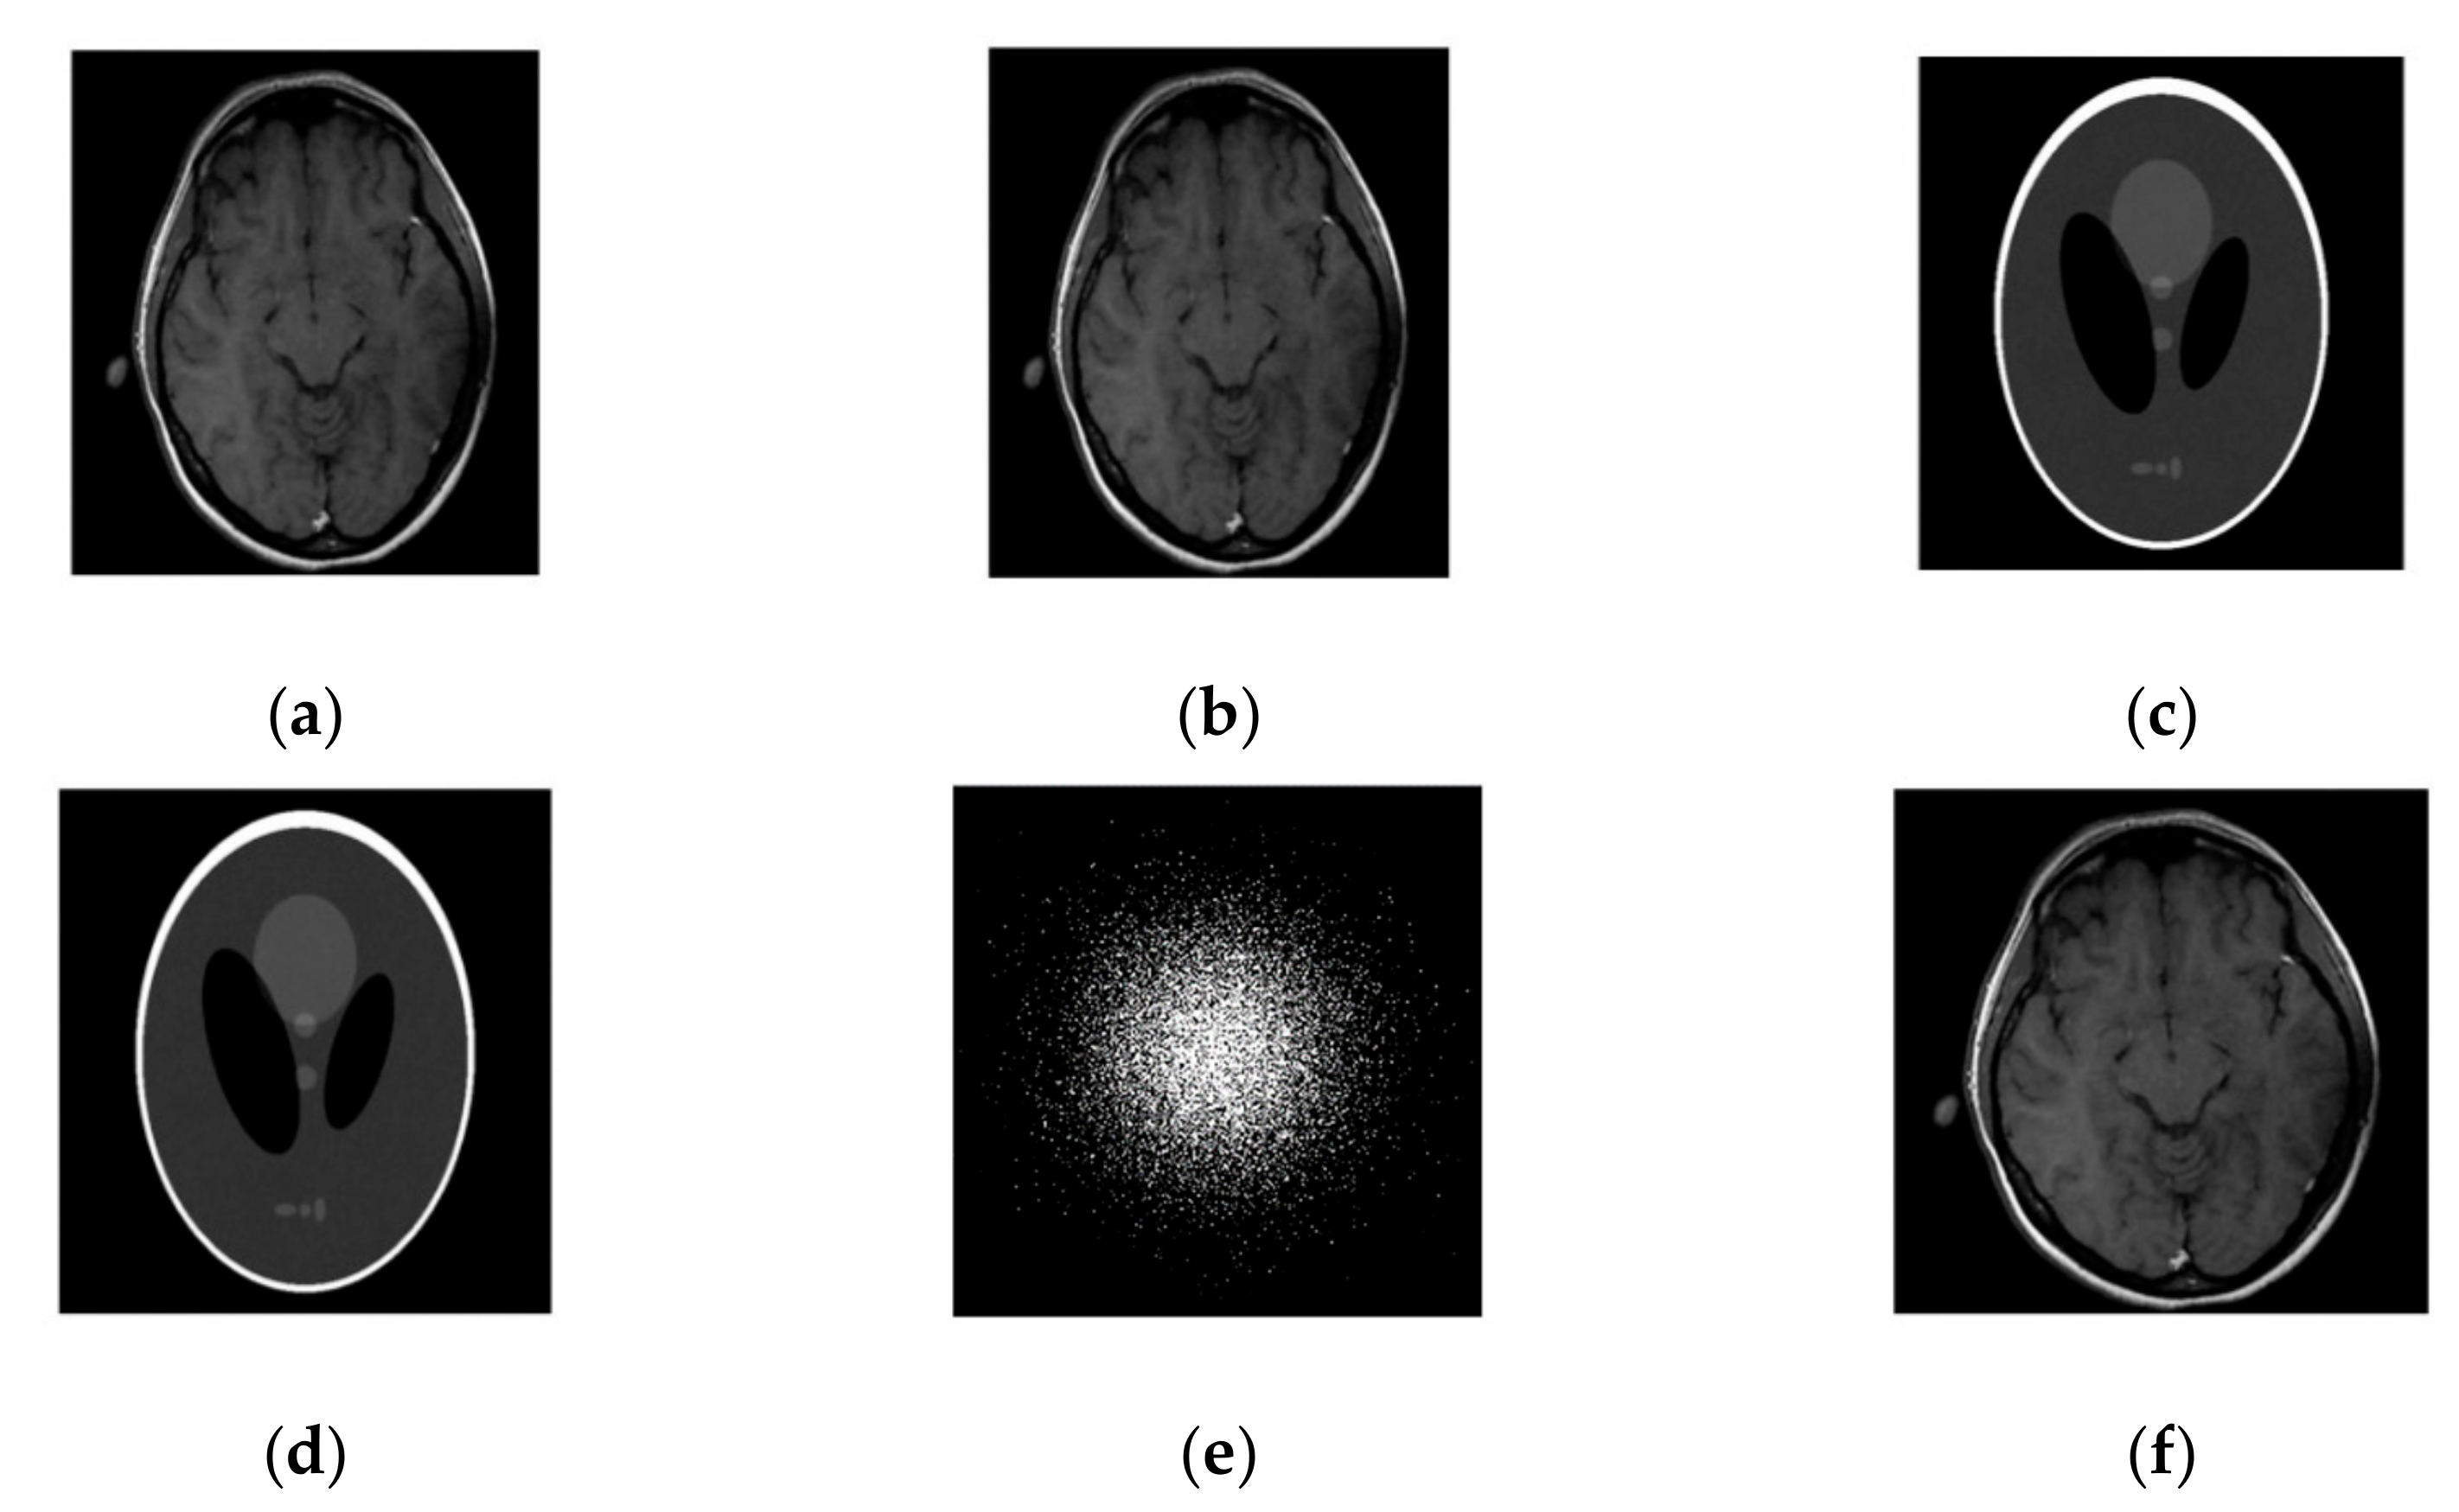

Figure 2. Images recovery for noiseless case. (a) Recovered MR image of brain by SiFo; (b) Recovered MR image of brain by DLMRI; (c) Recovered MR image of phantom by SiFo; (d) Recovered MR image of phantom by DLMRI; (e) Reconstruction brain image with zero filling; (f) Reference MR image for brain; (g) k-space sampling mask with 10 fold.

We first compared our proposed method with the DLMRI in a noiseless case. Figure 1 shows the performance of algorithm on brain and phantom image in noiseless scenario. Algorithm performance on a phantom and a brain image is evaluated using a 2D variable density random sampling of k-space. The dictionary learning algorithm (SiFo) reconstructed both the images free from artifacts and the aliasing effect. The results were achieved by running our algorithm for 15 iterations. The reconstruction with SiFo algorithm is clearer and sharper than with DLMRI.

3.1.2. HFEN

The SiFo performs better to capture the image of brain and phantom with fast convergence than DLMRI. This can be easily observed from Figure 1 and Figure 2, where our method showed better edges and sufficient features of reconstruction images.